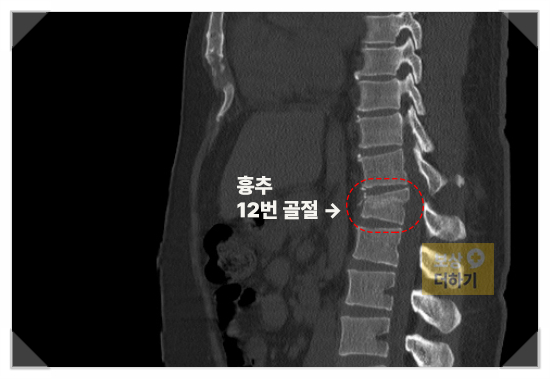

흉추12번 압박골절 (S22090)

정밀 검사에서 나온 결과는 흉추12번 압박골절이었습니다. 흉추 12번은 허리 바로 위쪽에 위치해 있으며, 상체 하중을 직접적으로 받는 부위라 압박 정도에 따라 장기적인 통증과 운동 제한이 남을 수 있습니다.

흉추 12번 압박골절 척추뼈가 눌려 압박되는 골절로, 낙상이나 추락 시 주로 발생 통증과 함께 허리를 굽히거나 펴는 동작에 제한이 생김